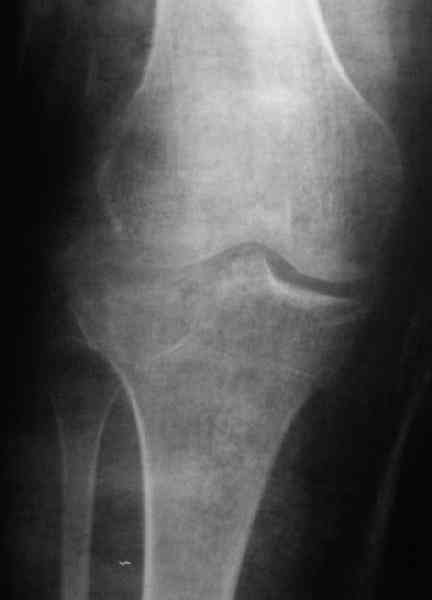

Застарелый перелом 41С3

Обратился больной 46л. 3-месяца назад в каком-то городке Дальнего Востока упал с высоты, сделана Р-графия, наложена гипсовая повязка, от предложенной операции отказался и уехал домой, дальше где и как лечился, не говорит.

Ходит при помощи двух костылей, жалобы на боли при нагрузке, в покое и при движении, без нагрузке боли нет, разгибание 175 гр, сгибание 90 гр, симптомов повреждения связочного аппарата к/с не определяется, от предложенного артродеза пока отказывается.

Уважаемые коллеги! какие будут мнения по поводу лечения, эндопротез недоступен. Заранее благодарю! С уважением Абдурашид.

По тактике лечения, более импонирует второй вариант, но наружная плато расколота и туда при нагрузке внедряется н/мышелка бедра, поэтому после дистракции как репонирвать: или стяжными винтами, или изогнутами спицами или субхондральная костная пластика?

У пациента основной проблемой является импрессионый перелом наружного мыщелка, уже неправильно сросшийся, по-видимому. Аппаратом закрыто можно только подправить угол на уровне метадиафиза. Что

улучшит разве что внешний вид конечности, но не решит основной проблемы - грубой деформации суставной поверхности.